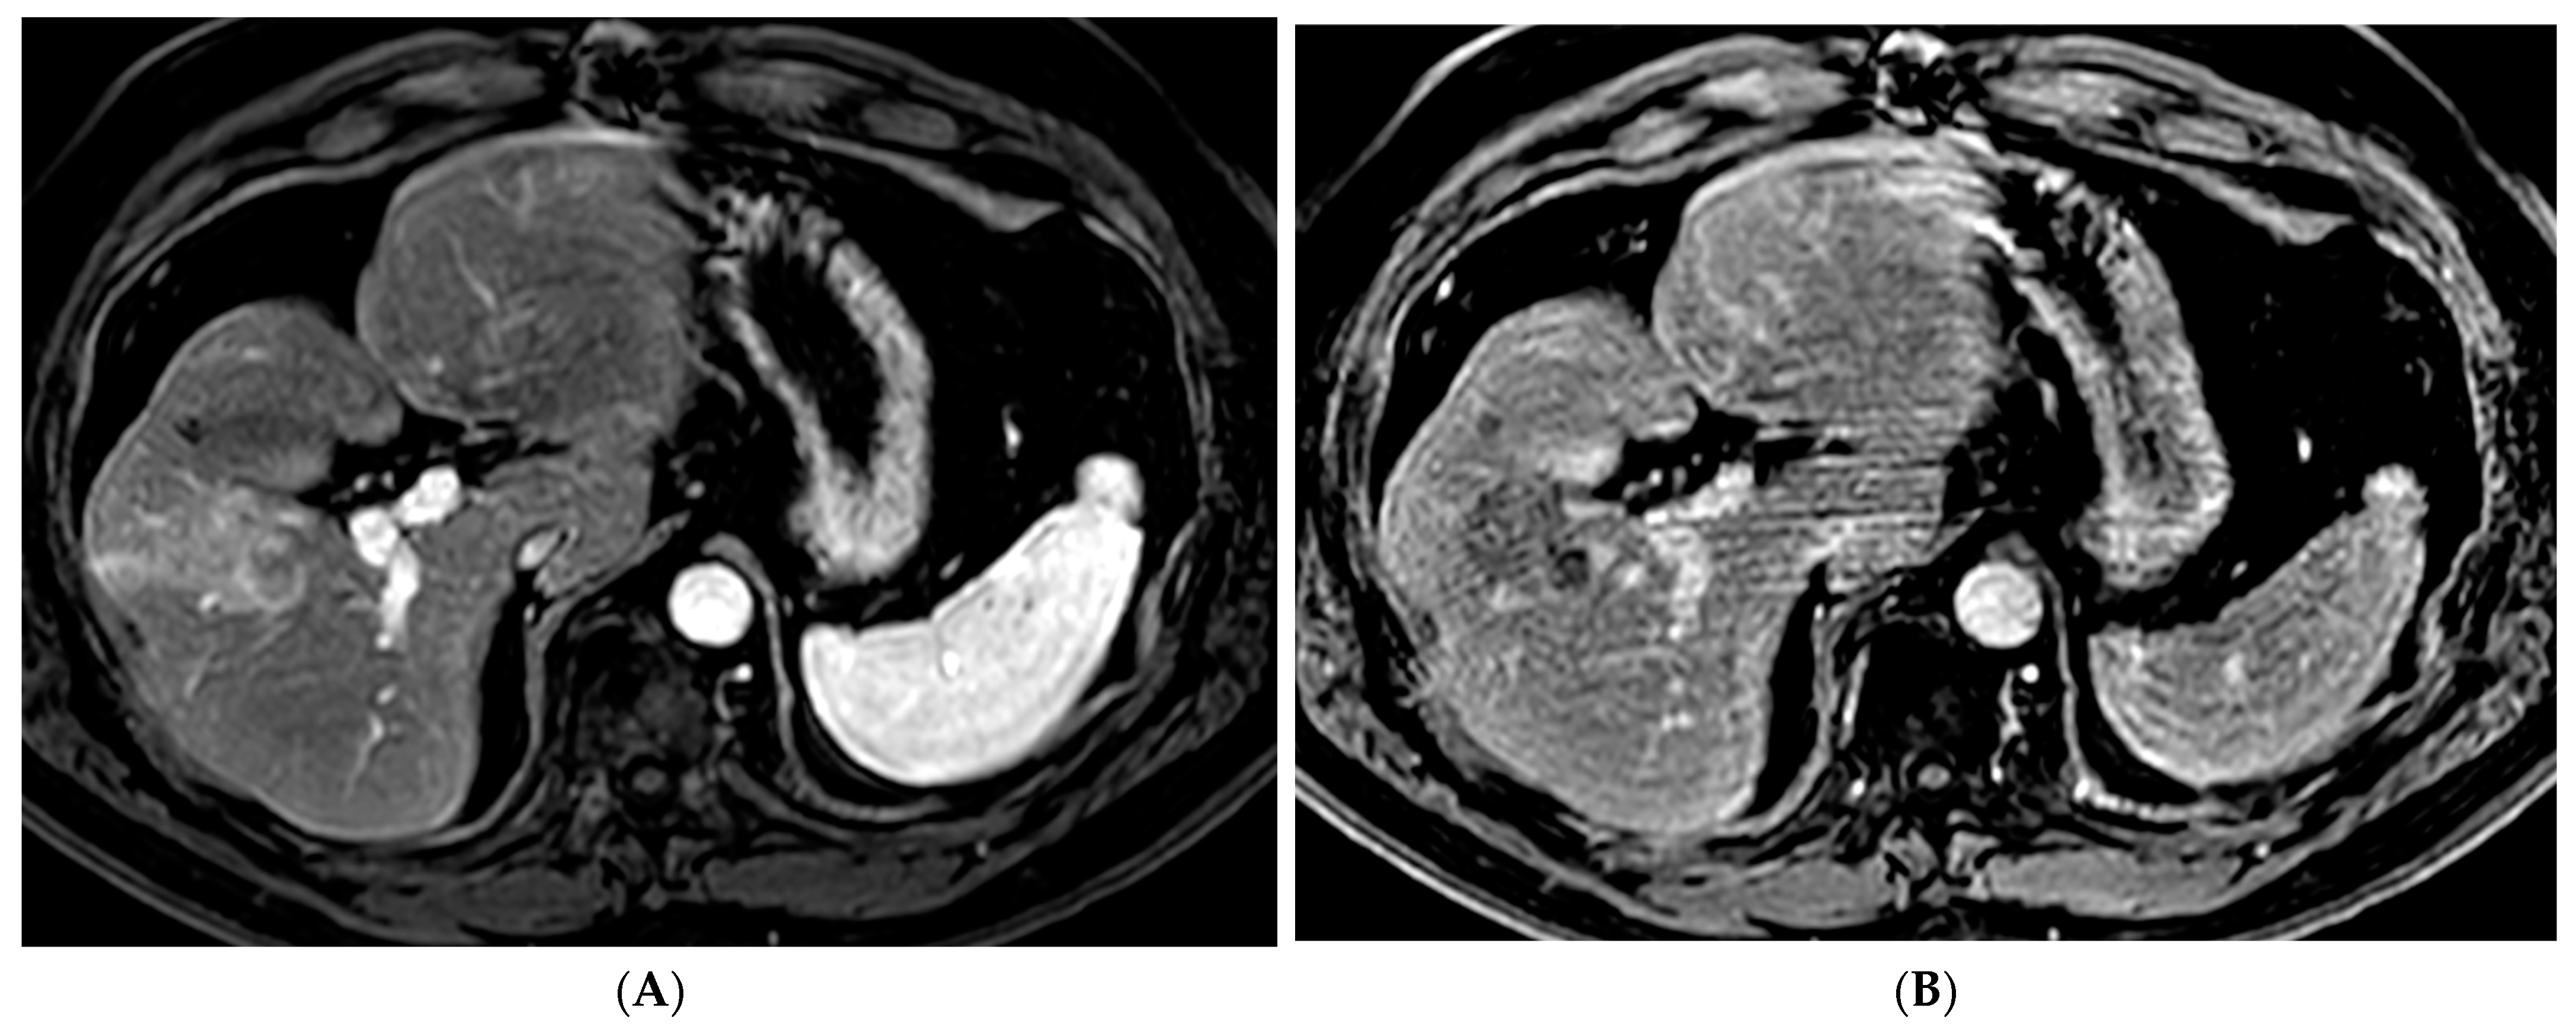

Percutaneous ablation is a curative option for patients with very early stage (BCLC 0) or early stage (BCLC A) HCC tumors < 3 cm who are not otherwise candidates for liver transplantation or resection [7]. Various techniques have been developed including RFA, MWA (Figure 1), cryoablation, and irreversible electroporation (IRE). These techniques require the tumor to be in a favorable location with a margin of normal liver tissue between the tumor and a critical structure. RFA is a heat-based technique that was developed alongside the electrocautery knife used by surgeons [8]. RFA involves creating a closed-loop-circuit with an RF electrode, generator, and grounding pads to produce an alternating current that agitates ions in the tissue leading to heat generation [8]. RFA is susceptible to the heat sink effect whereby adjacent vessels can dissipate heat and thus affect the ability to generate the necessary temperature for tumor necrosis, which is one of the pitfalls of this technique [8]. When compared with surgical resection, RFA has demonstrated similar local control and long-term survival with a significantly lower rate of complications as well as a shorter length of hospital stay [18,19,20].

Figure 1.

66-year-old woman with cirrhosis secondary to autoimmune hepatitis and HCC, treated with microwave ablation. (A) Arterial phase MRI showing a 3.5 cm arterially enhancing mass in the periphery of segment 7. (B) Delayed phase MRI demonstrating washout of the mass. Intraprocedural axial (C) and coronal (D) CT images demonstrating probe placement bracketing the mass. (E) Arterial phase MRI one month post ablation showing no residual viable tumor. (F) Arterial phase MRI one year post ablation demonstrating no residual or recurrent viable tumor and involution of the ablation cavity.